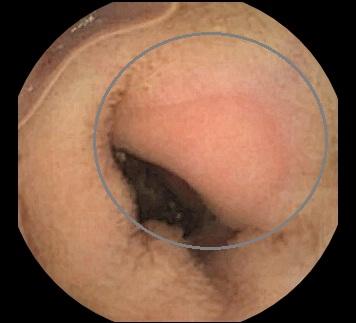

Клинические случаи: Эозинофильный энтерит

Пациент 3 лет с атопическим дерматитом, анемией, диареей с примесью слизи. При выполнении капсульной эндоскопии в тощей кишке обнаружены множественные розоватые участки слизистой оболочки овальной и округлой формы, с исчезновением ворсинчатого слоя характерные для эозинофильного энтерита. Sousa M, Pinho R, Proença L. Capsule Endoscopy in the Diagnosis of Eosinophilic Enteritis. GE Port J Gastroenterol. 2019 Aug;26(5):381-382. doi: 10.1159/000494095. Epub 2018 Nov 7. PMID: 31559331; PMCID: PMC6751447.